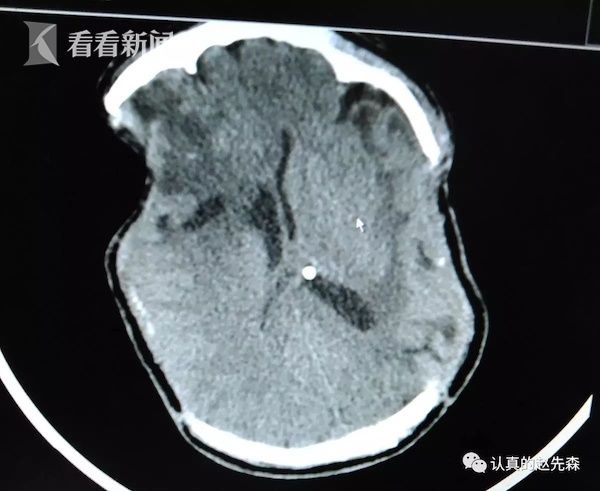

父亲被撞成植物人两年多,肇事司机买车买房就

父亲被撞成植物人两年多,肇事女司机买车买房

视频|父亲被撞成植物人两年多 肇事女司机买车